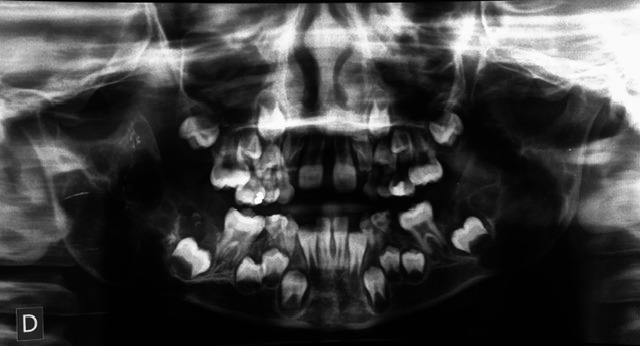

Materials and method: Clinical and radiographic examinations were used to evaluate 95 patients diagnosed with LCH, aged 0 to 16 years, who were referred to the Department of Comprehensive Pediatric Dentistry at the School of Dentistry, University of Buenos Aires. Clinical histories were prepared and informed consents obtained. Lesions were diagnosed by observation, palpation and biopsies, and grouped according to affected tissues into bone, mucosal, and bone-mucosal.

Results: 42.1% presented oral lesions, and in 14.73%, these lesions were the first manifestation of LCH. Ninety percent presented only bone lesions, while the remaining 10% presented bone-mucosal and mucosal lesions. In the single-system subtype, 52.5% presented bone lesions. In the multisystem subtypes (with or without risk organs), all three types of lesions were found. The association between age at which LCH was diagnosed and oral tissue involvement showed that bone-mucosal lesions occur in young children (average age 1.4 years) diagnosed with multisystem LCH. Oral mucosa was only affected in reactivations of the disease.

Conclusions: A high frequency of oral lesions was observed, which were sometimes the first manifestation of the disease, most often affecting bone tissue. Dentists can play an active role in the initial diagnosis of the disease.